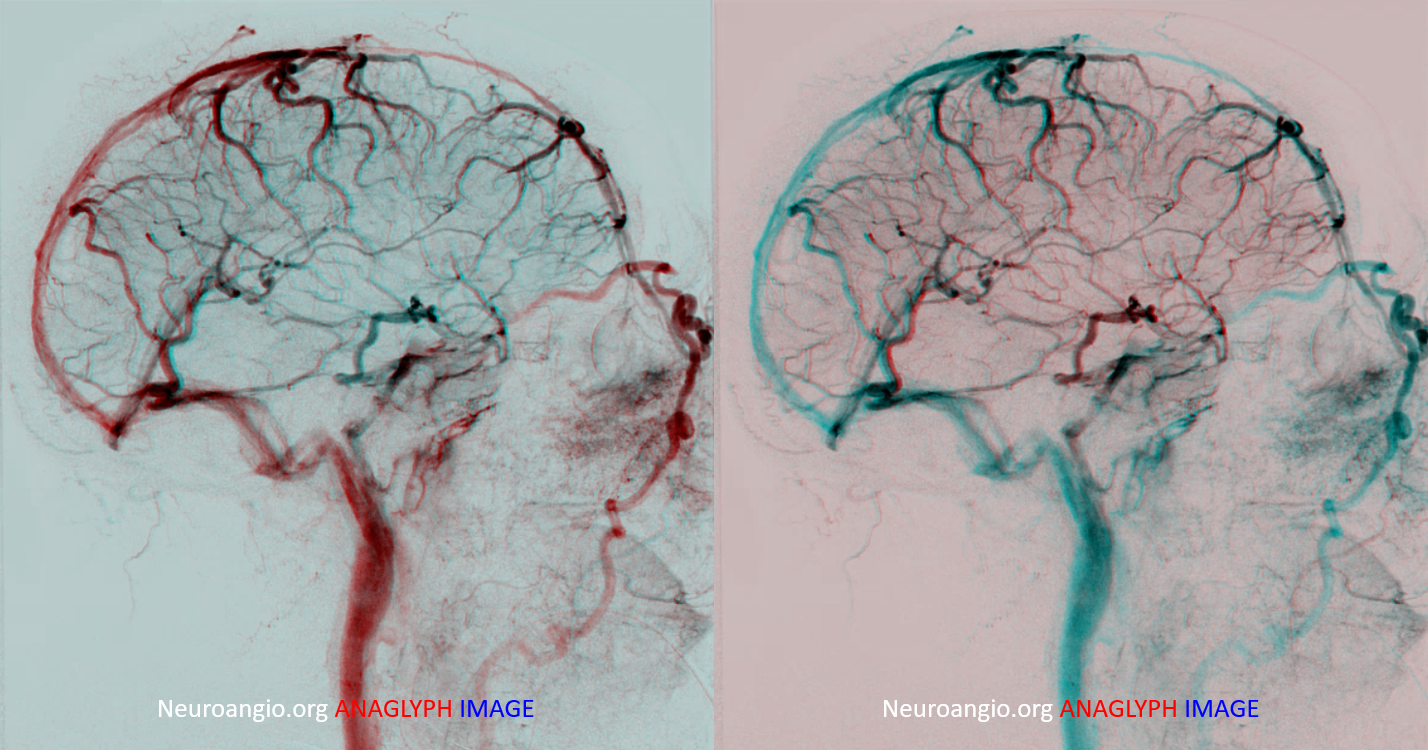

Anaglyph stereo